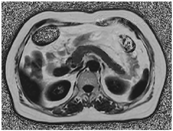

在ISP (Intelli Space Portall,Philips Healthcare)工作站上,选择Smart ROI软件,软件算法自动三维画取脂肪分数图全胰腺轮廓并手动进行轮廓的微调,软件自动计算全胰腺脂肪分数(fat fraction,FF)(图1)。